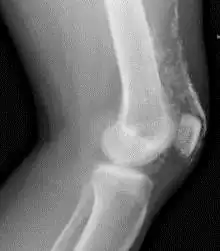

Röntgenfoto van een knie bij dermatomyositis.